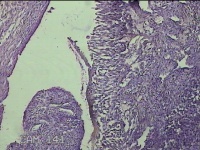

左侧卵巢黄体

性别

女

年龄

34岁

临床诊断

左侧卵巢黄体破裂

一般病史

下腹疼痛11小时。

标本名称

大体所见

灰白暗红色囊壁样组织3x2.3x0.3cm一堆,表面光滑,内壁高低不平,切面灰白暗红色,囊壁厚约0.1cm。